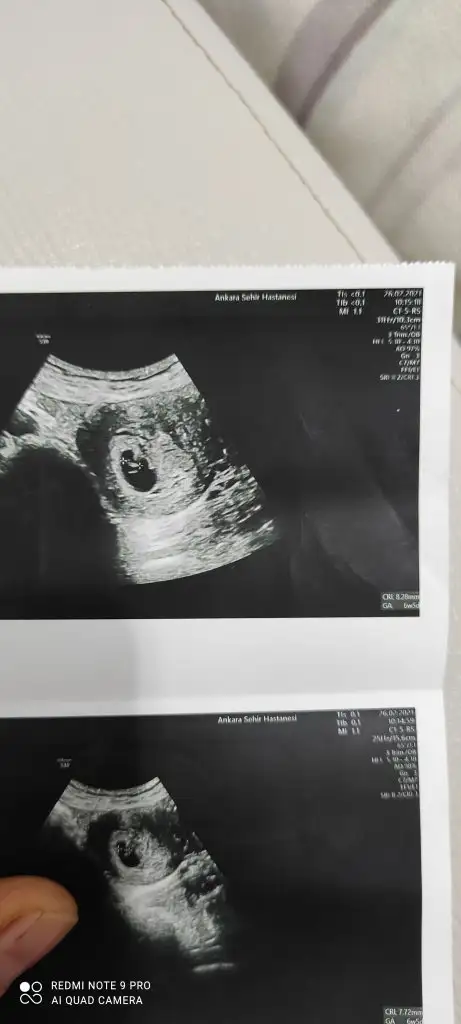

Cinsiyetini öğrendiniz miEki Görüntüle 2777702 Eki Görüntüle 2777703 Eki Görüntüle 2777704 6+4 7+4 11+4 yorumlayabilir misiniz? Henüz belli olmadı cinsiyetimiz